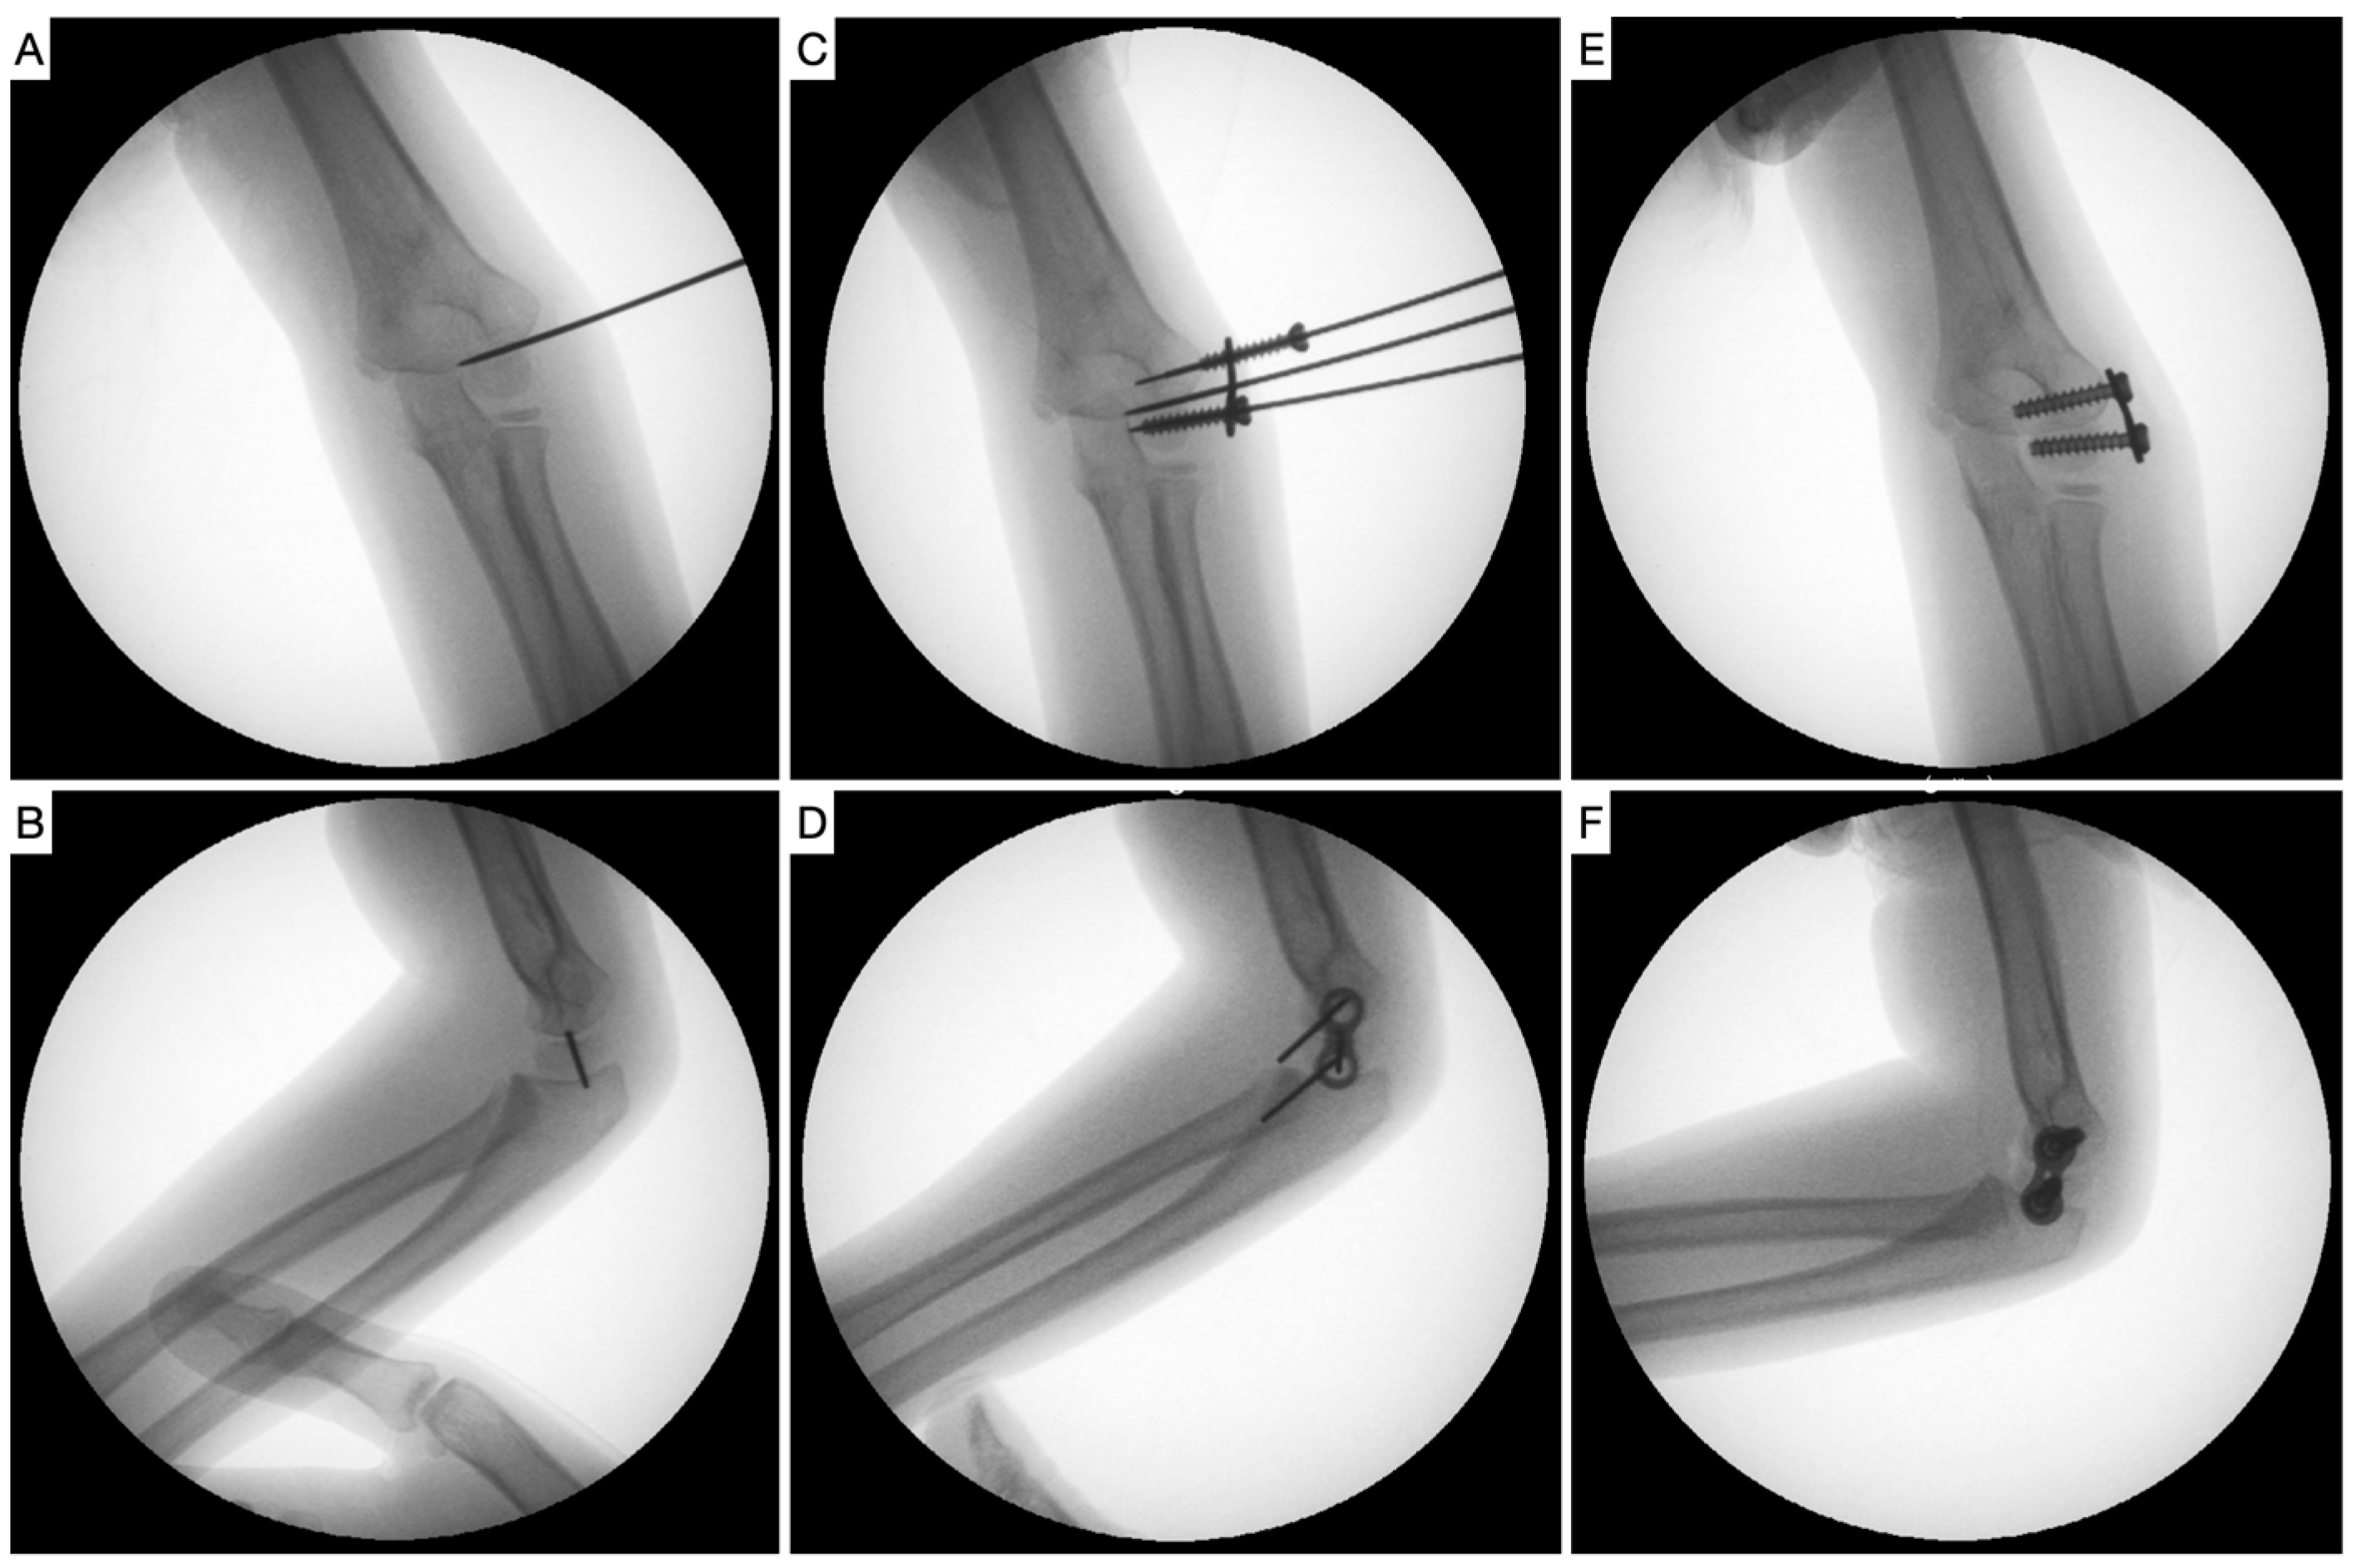

2. Materials and Methods

- Métaizeau, J.-P.; Wong-Chung, J.; Bertrand, H.; Pasquier, P. Percutaneous Epiphysiodesis Using Transphyseal Screws (PETS). J. Pediatr. Orthop. 1998, 18, 363–369. [Google Scholar] [CrossRef]